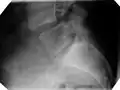

| X-ray of the lateral lumbar spine with a grade III anterolisthesis at the L5-S1 level | |

Classification by degree of the slippage, as measured as percentage of the width of the vertebral body:[14] Grade I spondylolisthesis accounts for approximately 75% of all cases.[6]

- Grade I: 0–25%

- Grade II: 25–50%

- Grade III: 50–75%

- Grade IV: 75–100%

- Grade V: greater than 100%

X-ray of measurement of spondylolisthesis at the lumbosacral joint, being 25% in this example